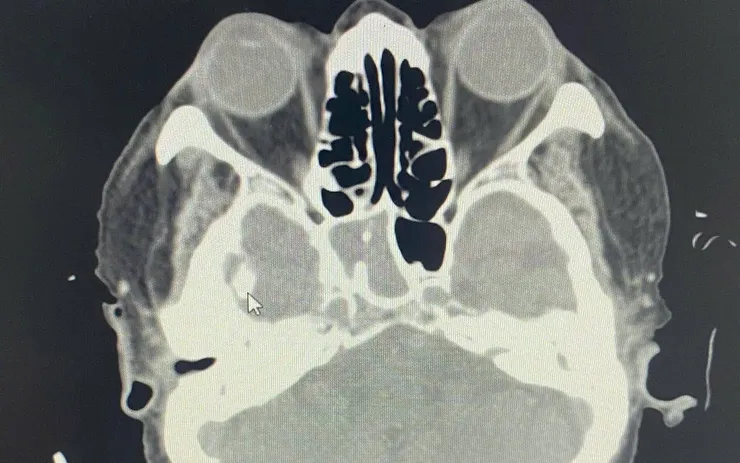

Người bệnh nhập viện trong tình trạng đau đầu dữ dội, kéo dài hàng tuần, không đi lại được. Kết quả chụp cắt lớp vi tính (CT) cho thấy xoang bướm phải mờ đặc, nghi ngờ viêm mủ hoặc nấm xoang. Đây là vị trí nguy hiểm, nằm sâu sát thần kinh thị giác và động mạch cảnh trong, rất dễ gây mù mắt, viêm màng não hoặc nhiễm trùng não nếu không được xử trí sớm.